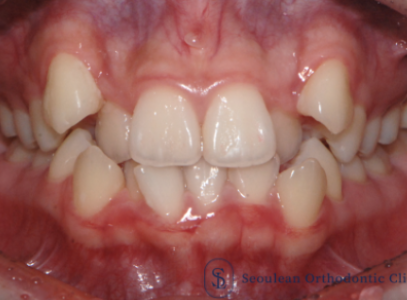

분당교정치과 / 치아 중심선이 어긋나서 고민이라면? – 실제 치료 사례